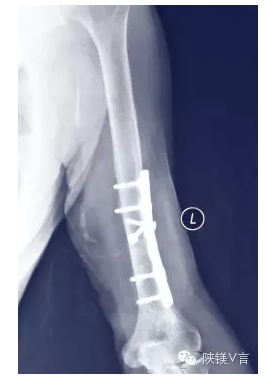

在医疗领域,首先被作为整形外科生物材料进入,因其很多的特点和属性,使植入物及类似应用程序成为非常具有吸引力的选择。早期,不锈钢、钛合金和钴铬合金等用于医用植入金属材料,其优势在于其良好的耐腐蚀性,可在体内长期保持整体的结构稳定。然而,植入这些金属材料后经过一段时间后,会让许多患者痛苦不已。因为这些材料无法与身体融合,有害金属离子溶出,引发人体过敏,病愈后需通过二次手术将其取出。

因此,能够生物降解的医用金属材料就成为植入材料未来的研究与发展方向,而与人体骨骼密度最为接近的合金有着独特的优势(合金密度约为1.7g/cm3、人体骨骼密度约为1.75g/cm3)。

合金容易加工成形,并且具有优良的综合力学性能以及独特的生物降解功能,而又是人体所必需的宏量金属元素之一,因此合金是医用金属材料的不二选择。合金的弹性模量约为45GPa,也接近于人体骨骼(10~40GPa),能有效地缓解甚至避免“应力遮挡效应”;合金在人体中释放出的离子还可促进骨细胞的增殖及分化,促进骨骼的生长和愈合。不仅如此,合金的加工性能远优于聚乳酸、磷酸钙等其他类型可降解植入材料,因此其在心血管支架方面也具有临床应用价值。